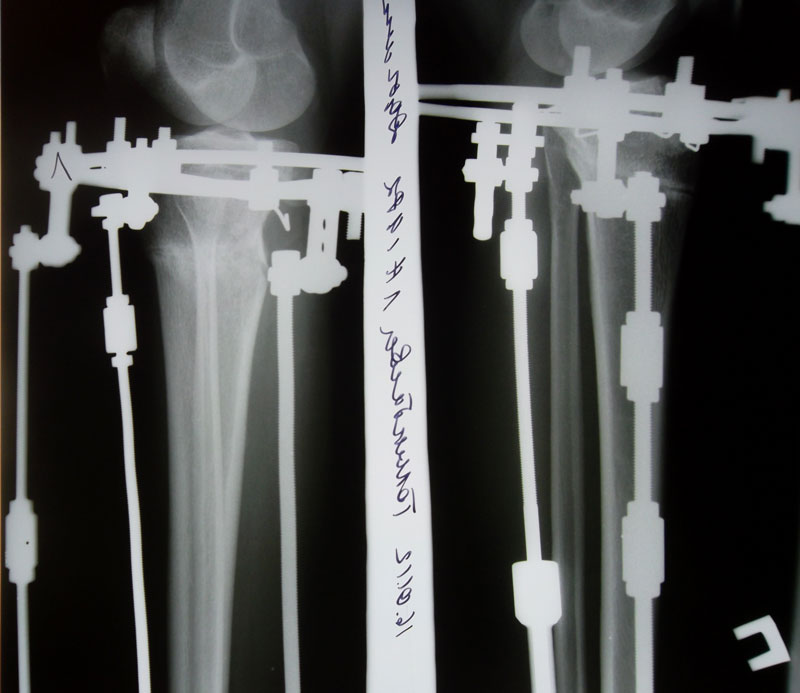

Рентгеновские снимки в день снятия аппаратов. 80 дней с момента операции.

Вложения

SAM_1450.JPG

SAM_1452.JPG